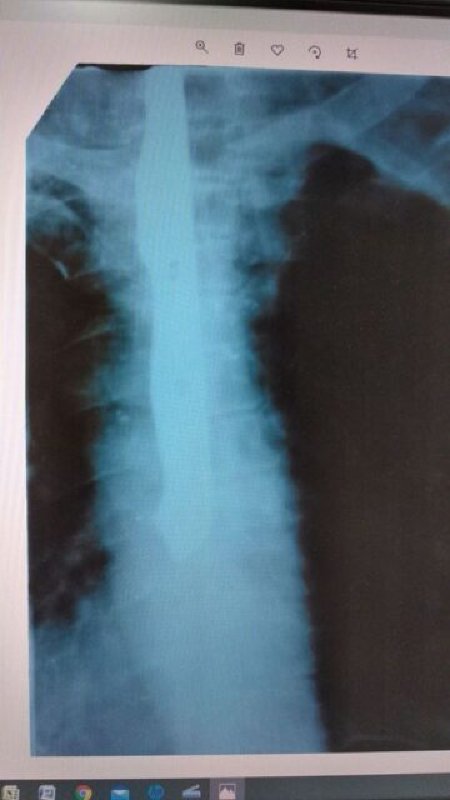

Удивлению даже самых опытных специалистов не было предела — при обследовании, на рентген снимке, в пищеводе наблюдался длинный тонкий предмет, похожий на нож. Об этом 4 марта сообщило каменко-днепровское издание "Знамя труда".

На днях в больницу в г. Каменка-Днепровская обратился мужчина с жалобами на сильную боль в горле, нарушения функций глотания и кровохарканье в течение 9 дней. Причину таких симптомов пациент объяснить не смог.